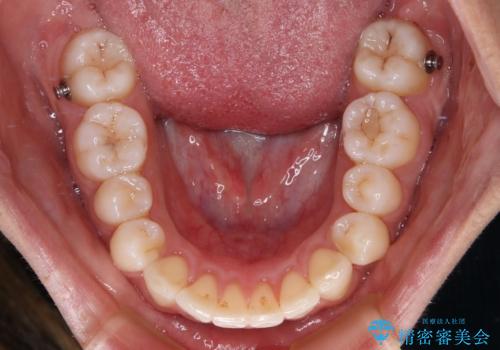

- 上下前歯が非接触となり、前方に突出していることを気にして来院された患者様です。

咬合力が強く、全体的に歯がすり減っているため、インビザライン単独での上顎歯列移動は困難と判断し、補助装置により上顎歯列を後方移動させ、その後インビザラインにて仕上げていくこととしました。

補助装置なしでも改善できる可能性はありましたが、補助装置で確実性を上げ、短期間できっちりと仕上げることができました。